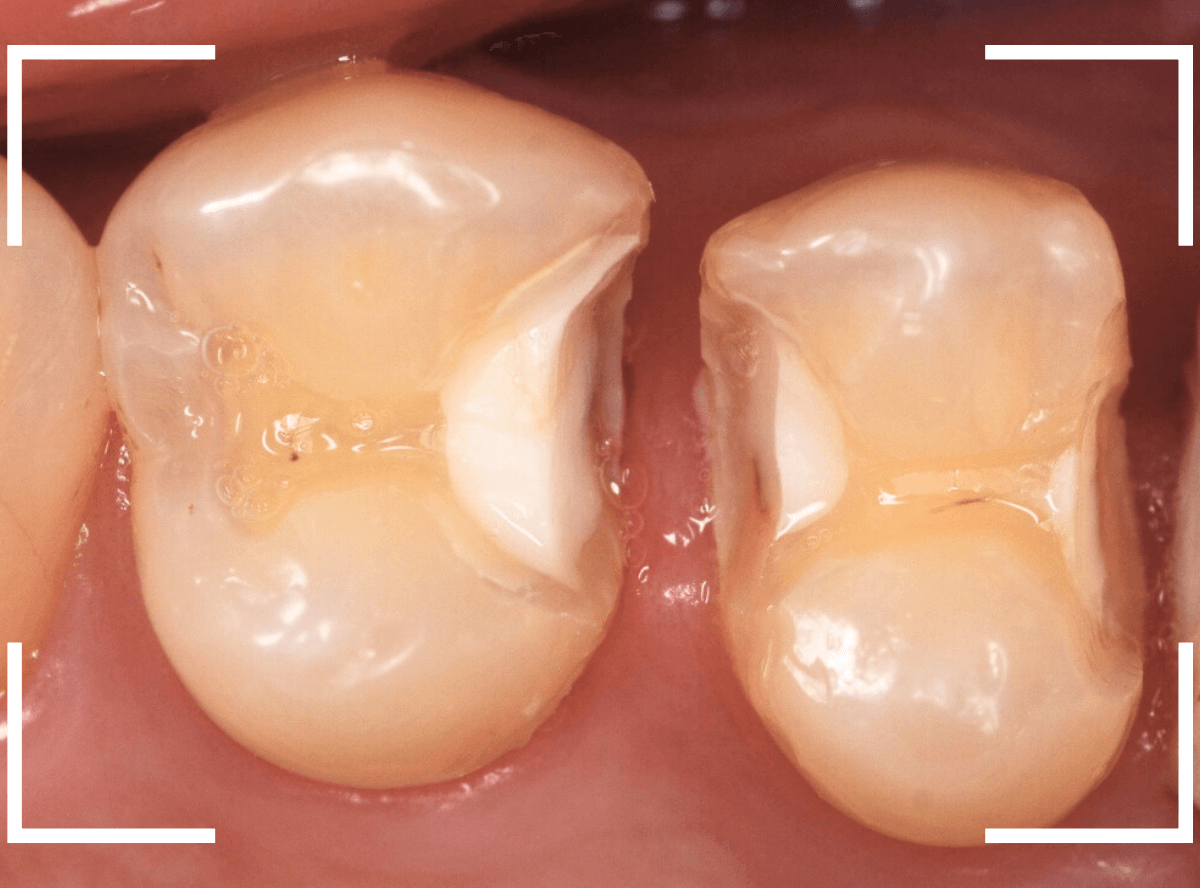

セラミック治療をご希望されましたので、

小臼歯をE-MAX・インレー、

大臼歯をジルコニア・インレーで処置することになりました。

治療後の状態です。

自然な仕上がりで、患者さんにもご満足いただけました。